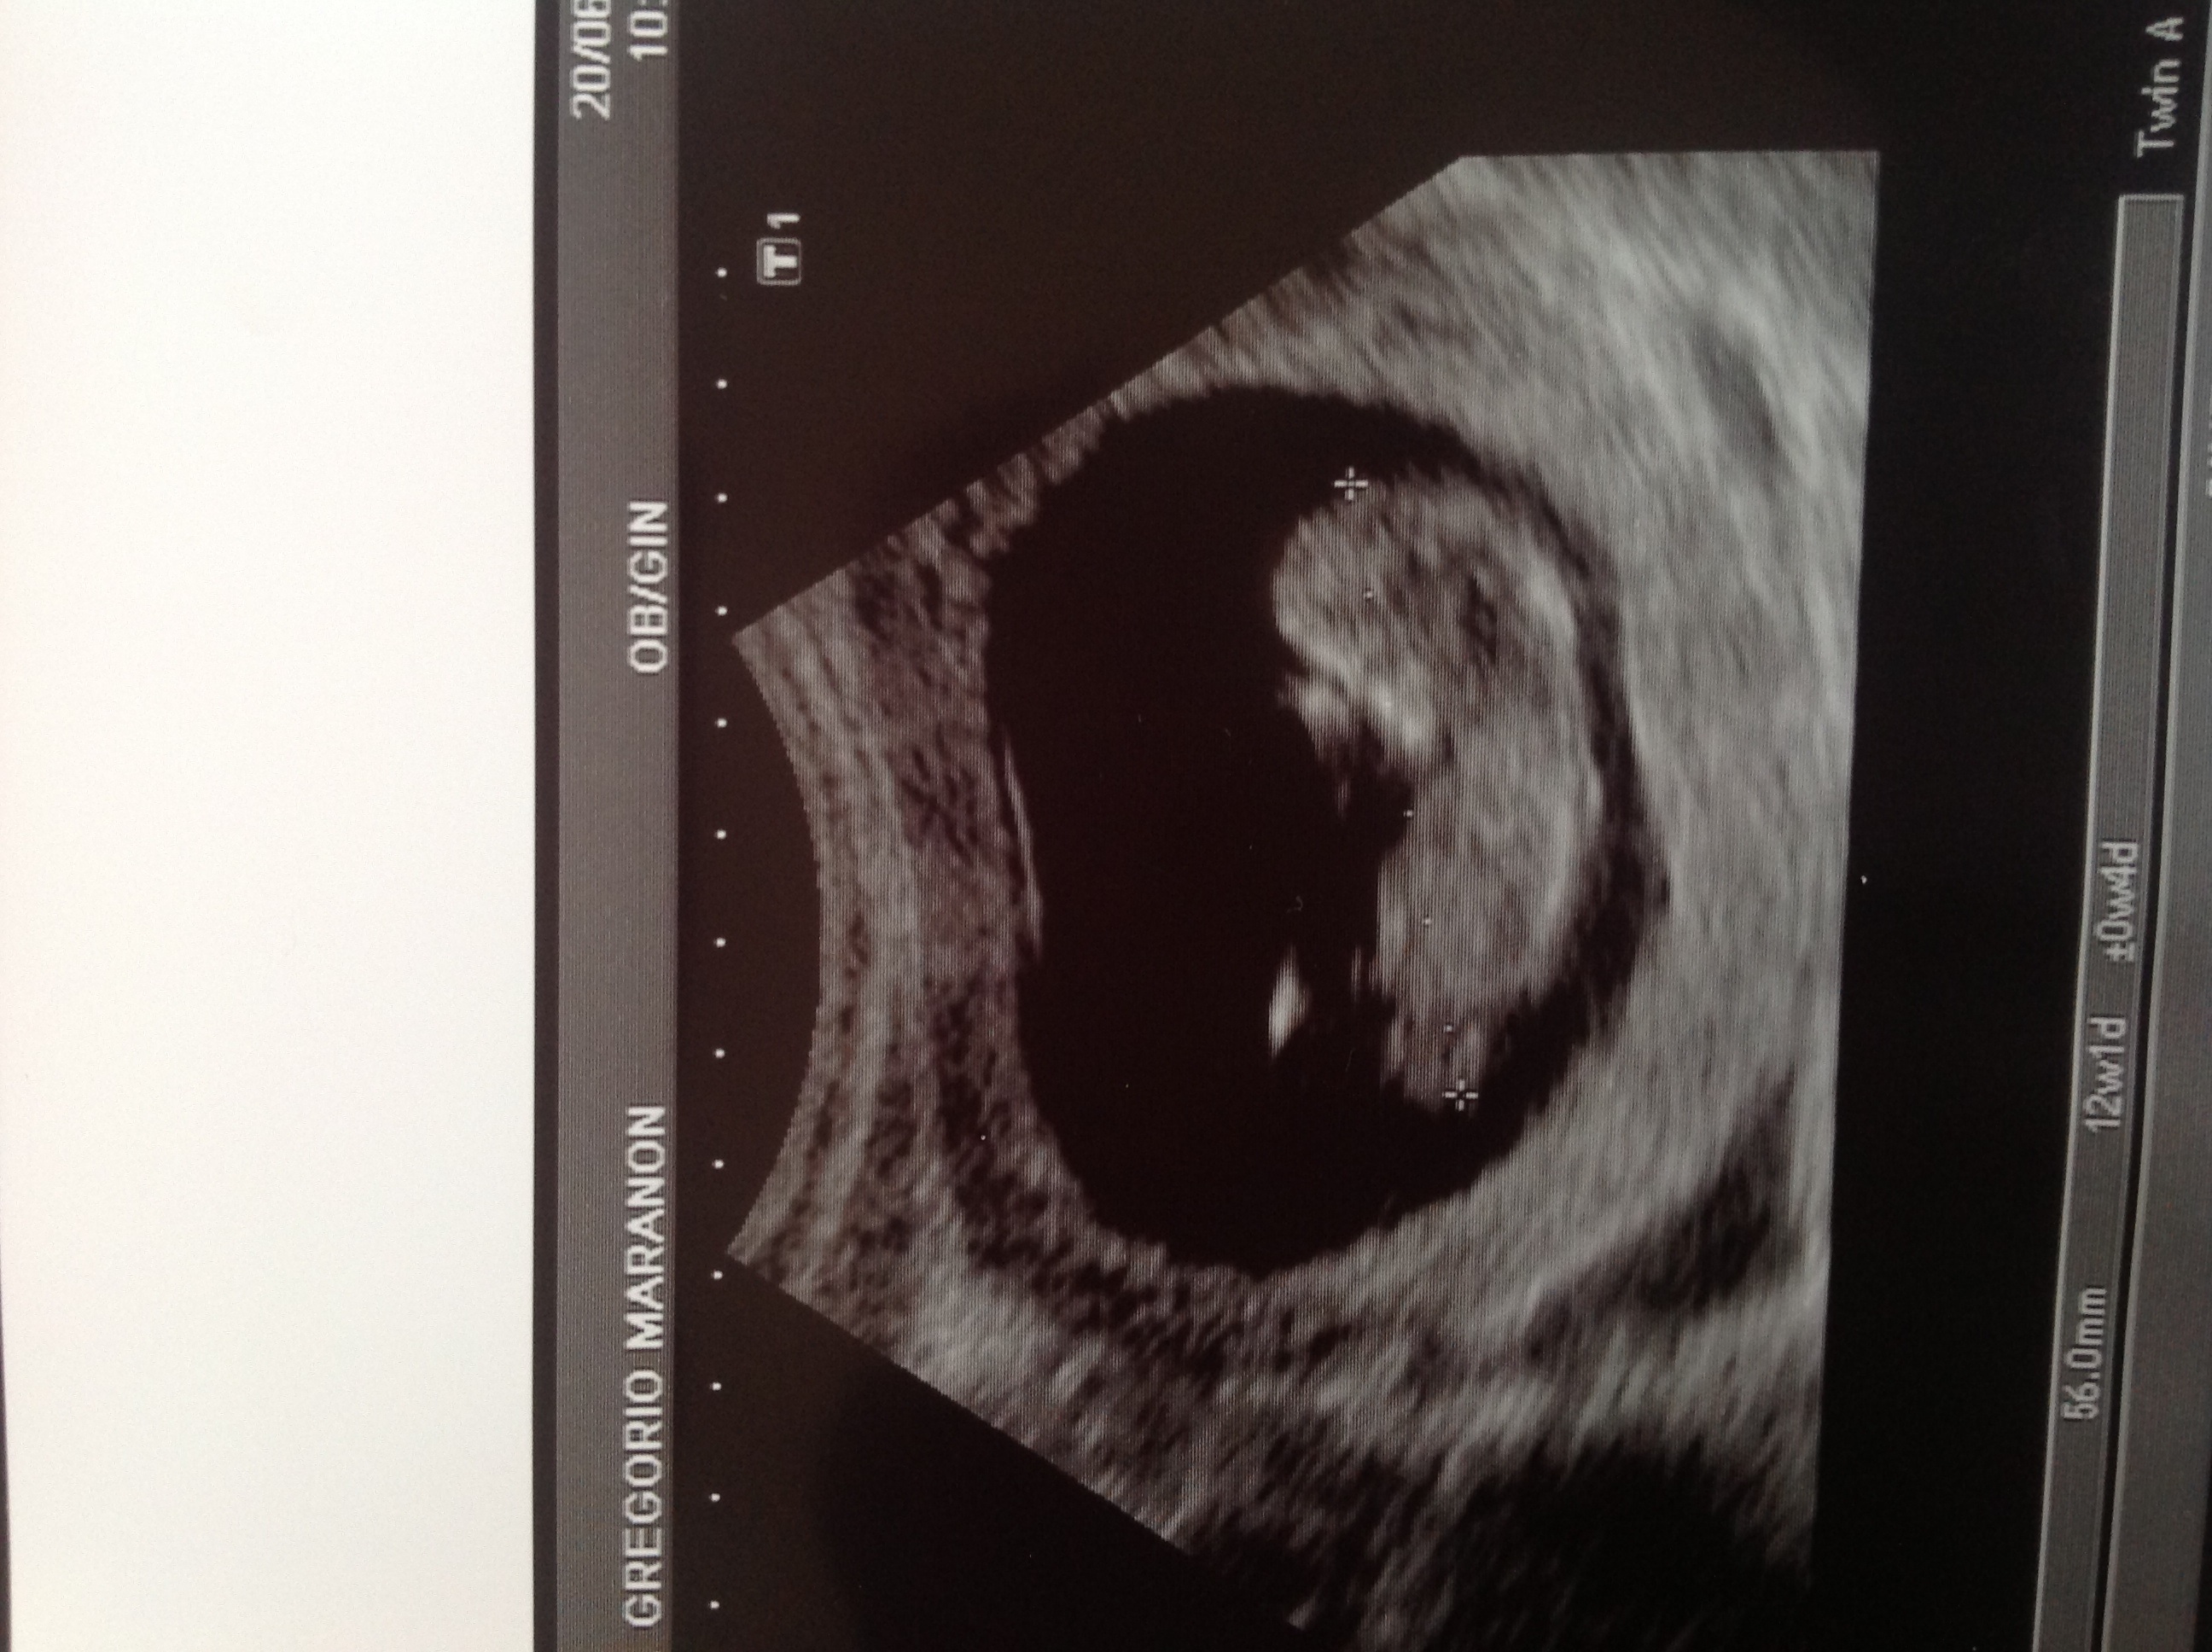

Slightly different shot

Attachment 11907

How funny that no one can see a nub in the second pic - that is the one I thought looked girly but perhaps I am not as good with nubs as I thought.

Based on first pic I'd totally guess girl. I wouldn't hazard a guess on the second pic as I don't really know what I'm looking at.

i think girl. First pic looks girly, second pic I thought maybe a little boyish but when I zoomed in on it, it looked girly too. :fx: :pinksperm: